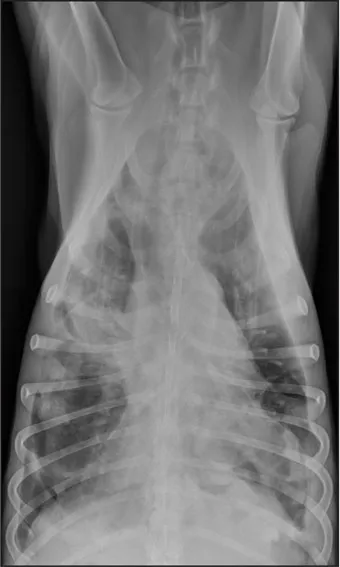

CASE 1.1 A 7-year-old neutered male Labrador Retriever who was hit by a car. You obtain these thoracic radiographs: Figs. 1.1a, b, left and right lateral projections, respectively; Figs. 1.1c, d, ventrodorsal and dorsoventral projections, respectively.

1.1a

1.1b

1.1c

1.1d